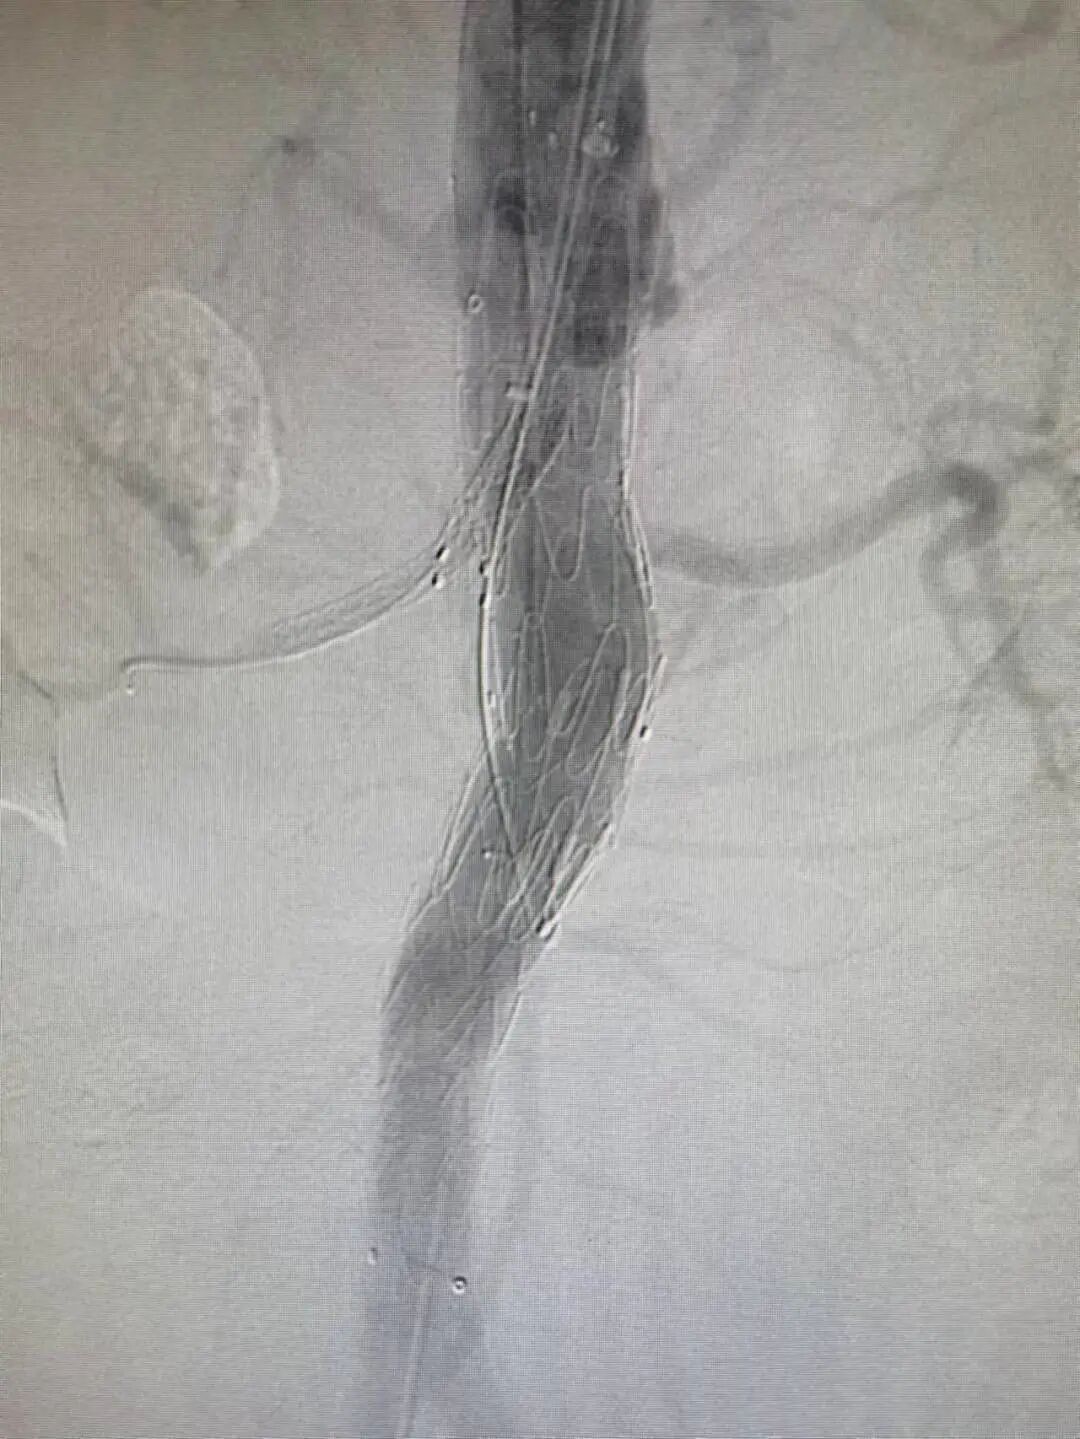

在杨维竹主任主刀、吴正忠主任一助,林俊清副主任及柯坤主治医师协助下,对患者行“腹主动脉瘤腔内隔绝+双肾动脉体外开窗+肠系膜上动脉烟囱术”。术中杨维竹主任及吴正忠主任行腹主动脉造影再次确定瘤体与双侧肾动脉及肠系膜上动脉关系,林俊清副主任及柯坤医师根据术前测量的数据,在覆膜支架相应位置进行“开窗”。

随后,“开窗”的支架被送入预先设计好的位置,准确释放。接着通过“开窗”口,对双侧肾动脉进行重建,同时使用“烟囱”技术重建肠系膜上动脉血供。操作完成后为老林行造影检查,腹主动脉瘤消失,双肾动脉及肠系膜上动脉顺行显影,此次介入手术成功完成。

▲分头行动,01分队造影定位,02分队体外“开窗”

▲覆膜支架体外开窗